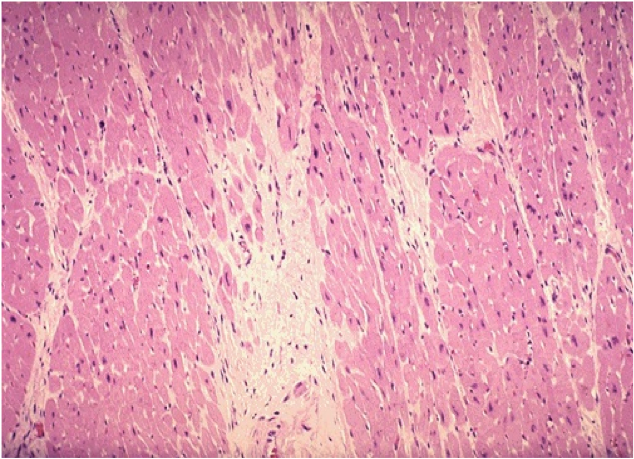

What is shown in this histo slide?

1-2 weeks after the MI

this is granulation tissue

macrophages are eating up the dead tissue (myocytes)